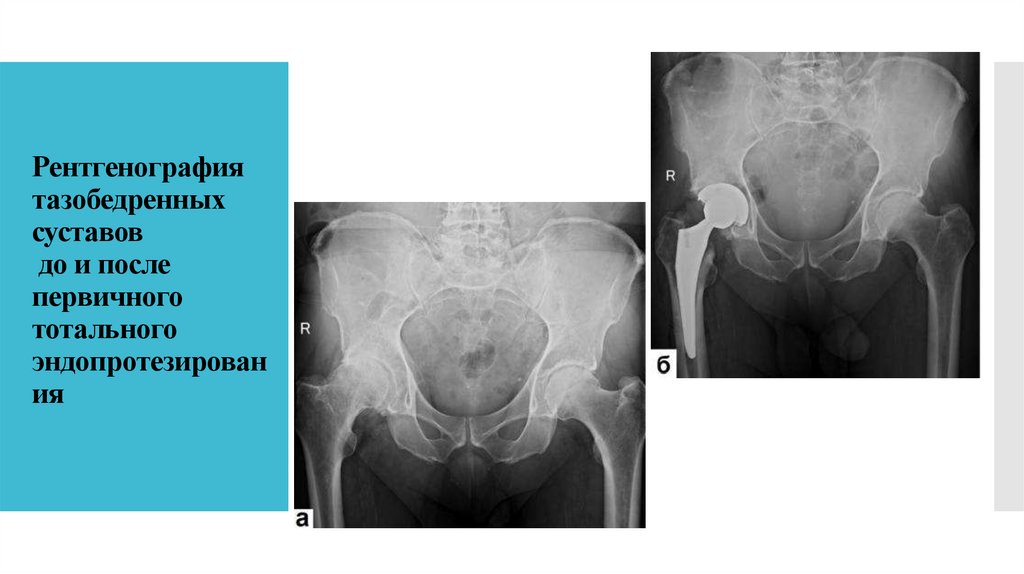

Рентгенография тазобедренных суставов до и после первичного тотального эндопротезирования

21. Рентгенография тазобедренных суставов до и после первичного тотального эндопротезирования

Рентгенография

тазобедренных

суставов

до и после

первичного

тотального

эндопротезирован

ия